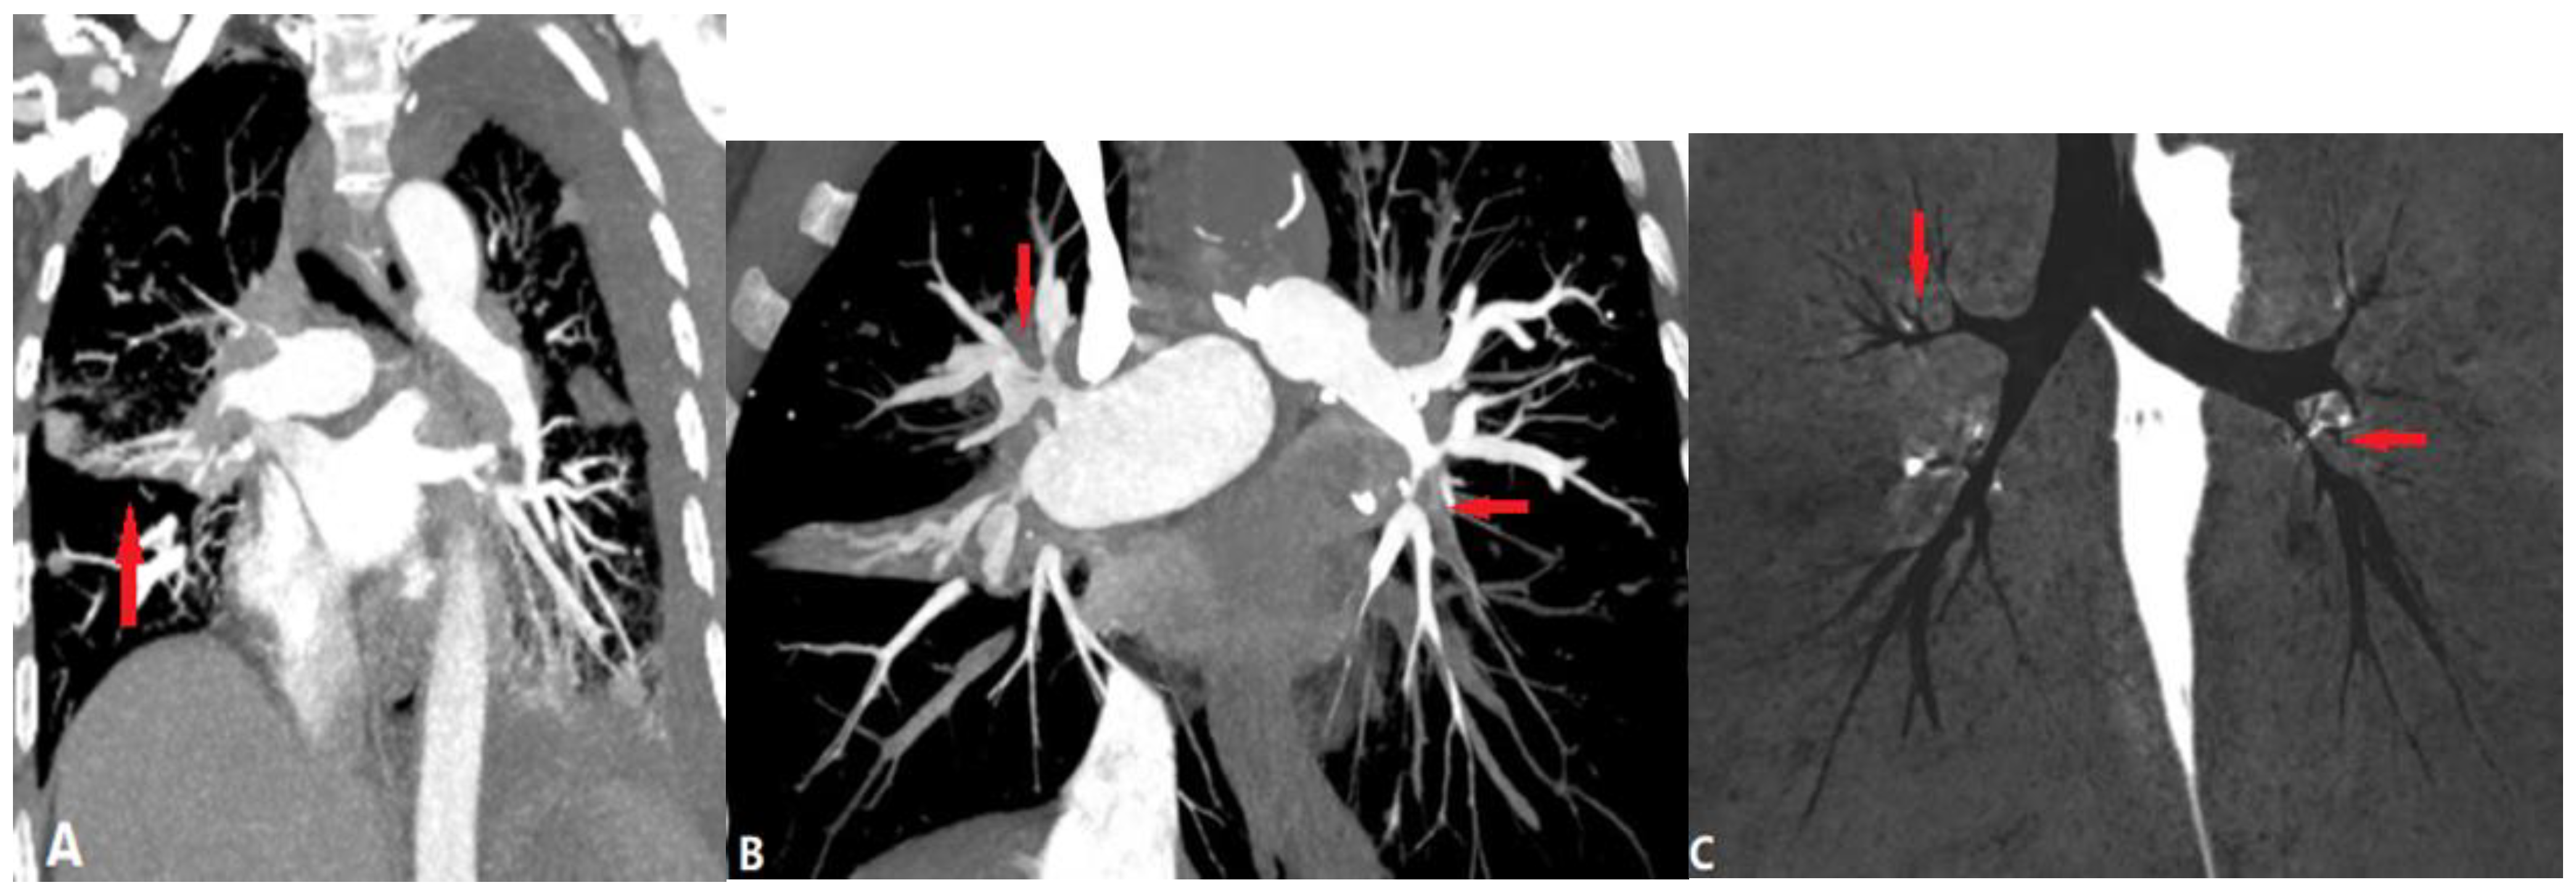

4.1.1. Pulmonary Thromboembolism (PTE)

4.1.2. In Situ Pulmonary Artery Thrombosis (PAT)